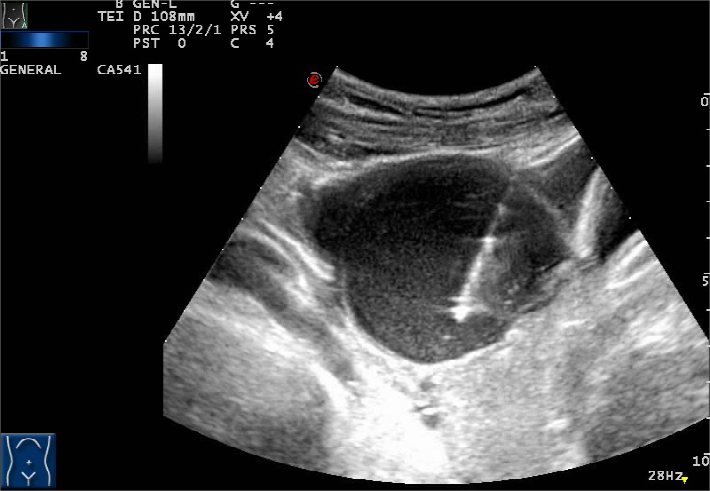

病史介紹患者,女,28歲,未婚未育,2年前因右卵巢囊腫(6157mm)在貴州某醫(yī)院行腹腔鏡下右卵巢囊腫剝除術。2022年2月復查B超提示:左側巧克力囊腫8.55.7cm,予地諾孕素口服保守治療效果不佳,隨訪至2022年10月,囊腫逐漸增大至9.25.78.8cm。由于患者不愿再次手術,且了解到超聲微創(chuàng)介入技術可以治療巧克力囊腫,遂來我們超聲介入微創(chuàng)治療中心咨詢。與患者充分溝通后,我們給患者進行了超聲引導下巧克力囊腫穿刺硬化治療術。手術過程術前超聲造影檢查:二維超聲顯示盆腔內大小約9.88.05.4cm的囊性暗區(qū),界清,內透聲差。超聲造影顯示囊壁光滑,未見明顯附壁結節(jié),囊內始終呈無增強,囊內未見分隔。1、常規(guī)消毒、鋪巾,用2%利多卡因局部浸潤麻醉。2、水隔離:實時超聲擇點定位及引導下,用18G穿刺針穿入盆腔,向盆腔注射400ml生理鹽水,分離出囊壁和周圍漂浮的腸管。3、抽出囊液:超聲實時引導下18G穿刺針置入囊腫內,抽出少量咖啡色濃稠液體,蛋白定性試驗為陽性。隨后向囊內多次注入生理鹽水反復沖洗、置換,直至抽出的液體清亮,并抽光囊內液體。4、硬化治療:向囊內注入50ml無水乙醇對囊壁沖洗3次,每次保留3分鐘后抽出。最后注入聚桂醇10ml,拔出穿刺針,結束治療。5、術后即刻超聲造影檢查:盆腔無明顯活動性出血,清晰顯示桑葚樣卵巢結構以及卵巢囊腫內保留的硬化劑。術后醫(yī)囑:1.局部壓迫止血、對癥治療。2.臥床休息8小時,心電監(jiān)護6h,密切觀察血壓及腹部情況。3.建議術后第二天,第1、3、6、9、12個月復查超聲。技術優(yōu)勢超聲引導卵巢巧克力囊腫微創(chuàng)治療術與其他手術相比,具有更加微創(chuàng)、費用低等優(yōu)勢,對有生育要求的女性來說,能最大程度保留卵巢功能。